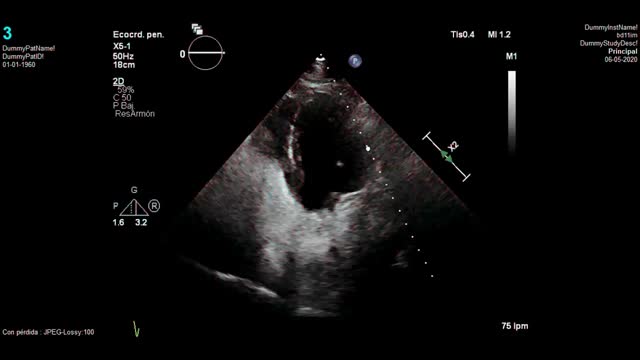

Tras 10 días ingresada con uso de VMNI nocturna se consigue mejoría de la hipercapnia, pero persiste con hipoxemia refractaria (precisa FiO2 60% para mantener SatO2 >90%). Sospechando un shunt derecha-izquierda por foramen oval permeable, se solicitó una ecocardiografía urgente con suero salino agitado que confirmó la sospecha: había paso precoz de moderada cantidad de burbujas hacia cavidades izquierdas. A su vez, persistían signos ecocardiográficos sugestivos de hipertensión pulmonar significativa, con una presión arterial pulmonar sistólica estimada de 80mmHg. Tras estos resultados se añadió sildenafilo (20mg/8h) y se retiró la VMNI con mejoría clara de la saturación, pudiendo ser dada de alta 3 días después del inicio del fármaco, que se mantuvo al alta. No se consideró en este caso intervención quirúrgica del foramen oval dada la mejoría clínica tras retirada de la VMNI y el inicio del sildenafilo, en una paciente con bastante comorbilidad.